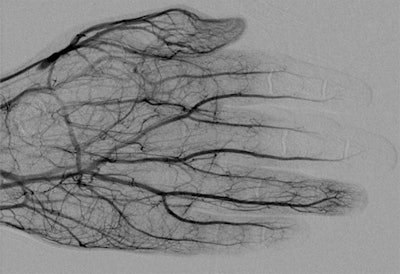

Digital subtraction angiography image obtained approximately 24 hours after 1 mg/h IA tPA infusion, 500 U/h heparin via peripheral IV, and daily oral aspirin (81 mg) shows improved perfusion of digital arteries, albeit with suboptimal vascular blush of distal second and third phalanges. All images courtesy of the American Journal of Roentgenology.

Digital subtraction angiography image obtained approximately 24 hours after 1 mg/h IA tPA infusion, 500 U/h heparin via peripheral IV, and daily oral aspirin (81 mg) shows improved perfusion of digital arteries, albeit with suboptimal vascular blush of distal second and third phalanges. All images courtesy of the American Journal of Roentgenology.Lee and Higgins sought to evaluate the efficacy of intra-arterial and intravenous tPA therapies to treat these injuries and reduce the need for amputation. They reviewed 157 studies, finally including 16 that described using intra-arterial and intravenous tPA. The studies consisted of 209 patients with 1,109 digits at risk of amputation. In 15 of the 16 studies, patients were initially evaluated using digital subtraction angiography (DSA) or triple-phase bone scans.